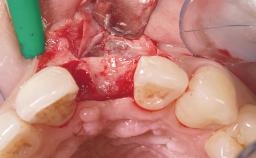

Immediate Placement of an Implant in a Maxillary Right Central Incisor Site

A 30-year-old female patient was referred to the office for the treatment of tooth 11. Her chief concern at the initial visit was to inquire, “Why is my tooth pink?” Upon clinical examination, it was determined that tooth 11 had a previous history of trauma and that the clinical crown had become noticeably pink in color as a result of internal resorption. This diagnosis was confirmed radiographically, indicating a large radiolucency involving the central and distal portions of the clinical crown. It was determined that restoration of this tooth was not possible, and that extraction was indicated. The presence of a mid-line diastema, which the patient wanted to reproduce, directed the treatment plan for tooth replacement utilizing a dental implant.

Placement Protocol Immediate implant placement

Tooth Site Maxillary incisor or canine

Socket Morphology Single-root socket

Socket Integrity Sufficient, with intact bone walls

Bone Volume Sufficient, with intact walls